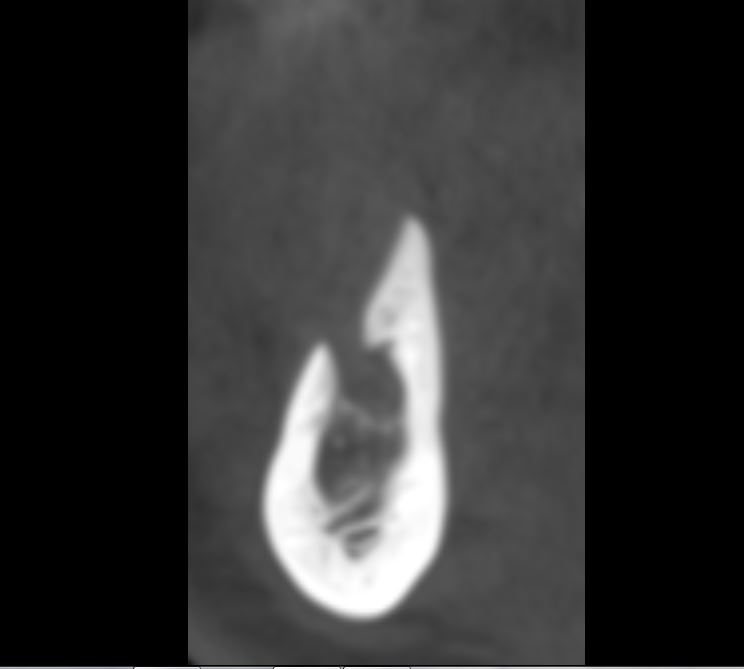

Da questo taglio di TAC puoi vedere la superficialità del foro mentoniero.

Inoltre, era presente un forame accessorio molto mesiale dal quale, con buona probabilità, usciva una branca collaterale del nervo mandibolare che innervava chissà quale zona del labbro o del mento… meglio non tagliarla, non credi?